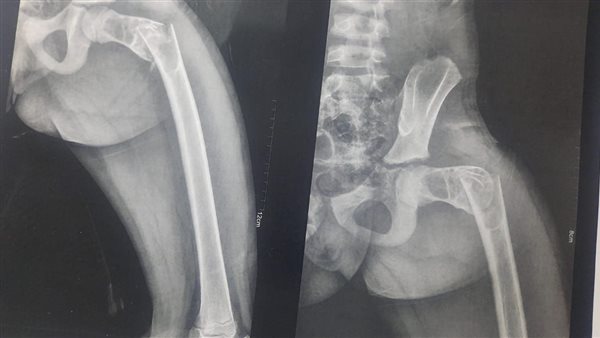

نجح فريق طبي بقيادة الدكتور إيهاب عباس أخصائي العظام، والدكتور أحمد خطاب طبيب الزمالة، والدكتور وائل الحبشاوي استشاري التخدير بالمستشفى، تحت إشراف الدكتور محمد يحيي مدير المستشفى، والدكتور محمد شبراوي رئيس قسم العظام بالمستشفى، بإجراء عملية ترقيع عظمي وتركيب بدائل عظام بالفخذ لطفل يبلغ من العمر ١٠ سنوات.

أوضح الدكتور هاني جميعه بأنه تم استقبال الطفل بقسم الاستقبال والطوارئ بالمستشفى، يعاني من كسر وورم بالفخذ، وتم على الفور توقيع الكشف الطبي عليه، وإجراء كافة الفحوصات المعملية والأشعات اللازمة له، وتجهيز غرفة العمليات، وتم إزالة الورم أولاً، ومن ثم عمل ترقيع عظمي وتركيب بدائل عظام والتثبيت بواسطة شرائح وأسلاك، والحالة الآن بفضل الله مستقرة وبحالة جيدة، وتتلقى الرعاية بقسم العظام بالمستشفى.